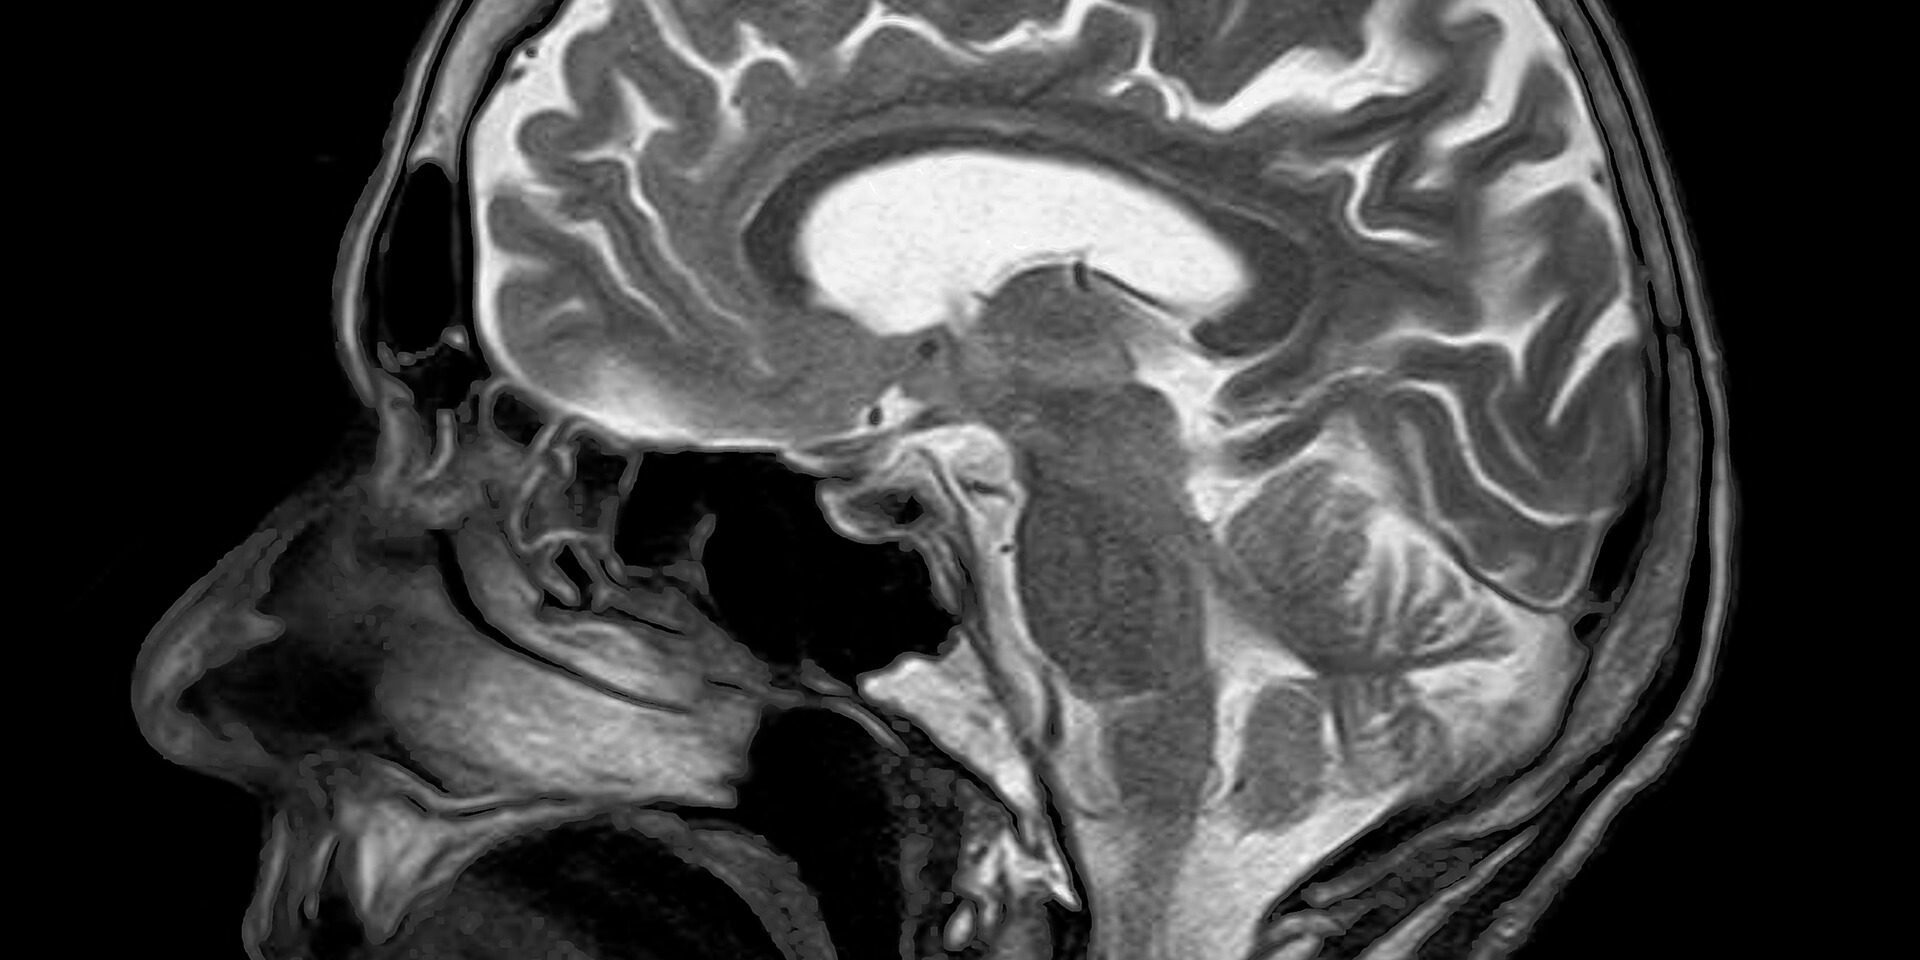

L’ostéopathie après une commotion cérébrale

La définition médicale d’une commotion cérébrale est un trouble soudain et rapidement résolutif du fonctionnement du cerveau, secondaire à un traumatisme crânien ou tout impact sur le corps, transmettant à l’encéphale des contraintes d’inertie importantes.

L’ostéopathe palpe la surface du crâne où à eu lieu l’impact et regarde également les différentes répercussions qu’il y aurait pu avoir sur toute la boite crânienne.